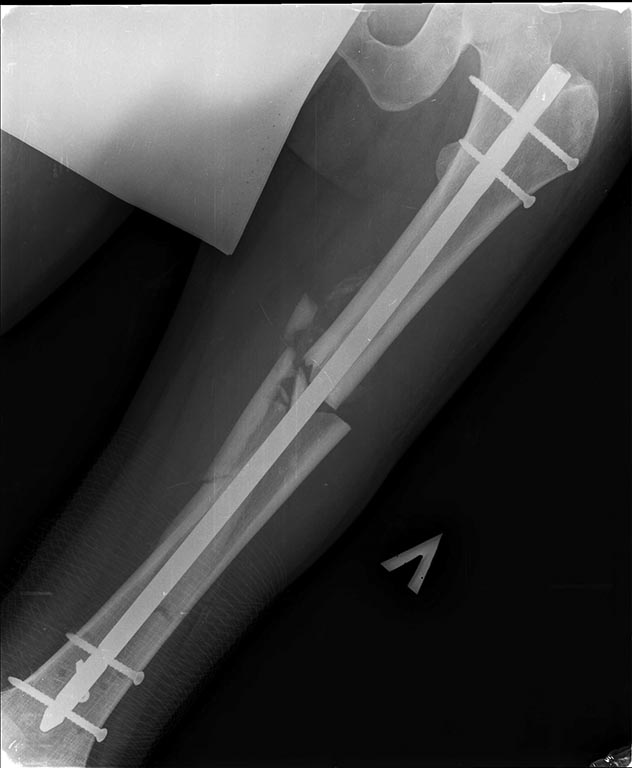

Добрый день уважаемые коллеги. Вашему вниманию представляю

пациента(мужчина, 30 лет).

Тяжелая сочетанная травма 7 мес. назад. Из скелетной травмы: открытый

перелом бедра, открытый перелом дистального метаэпифиза левого плеча,

закрытый перелом шейки левого плеча). Все повреждения были

прооперированы.Бедро синтезировано штифтом Остеомед d-11мм.

Раны зажили первично. Пациент после выписки впервые появился на

контрольный осмотр ч/з 7 месяцев. Жалобы на боли в левом бедре при

нагрузке, ощущение подвижности в месте перелома.

Передвигается без дополнительных средств опоры. Локально: отека левого

бедра нет, п/операционные рубцы без признаков воспаления. движения в

суставах левой н/конечности в полном объеме, безболезненны.( все снимки,

первичные, после операции и на сегодня